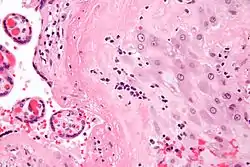

| Micrograph of a chronic deciduitis, showing the characteristic plasma cells. H&E stain. | |

Chronic deciduitis is a type of long-lasting inflammation that arises in pregnancy and affects the endometrial stromal tissue (decidua).

It is associated with preterm labour.[1] The diagnosis rests primarily on the presence of plasma cells.[2]